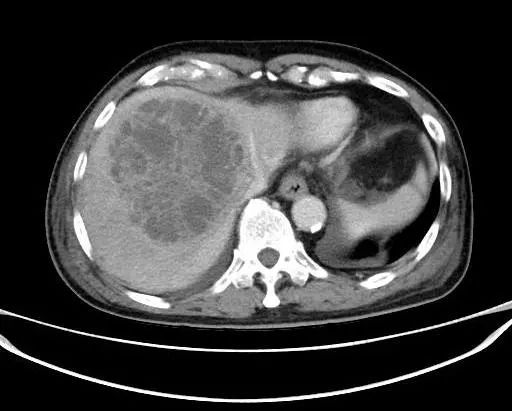

经过数天抗感染治疗,ct复查示脓肿持续增大,白细胞居高不下,肝肾功能出现异常,为了防止病情进一步发展,普外科与超声医学科陈曼主任会诊后认为急需进行超声引导下肝脓肿穿刺置管引流,需要对抽出的脓液进行细菌培养和药物敏感试验,以便选用有效的抗生素进行治疗,同时置管引流脓液。

术前对病灶进行充分评估,并做了超声造影,肝脓肿较成人拳头略大,內见较多的分隔。

于是,我们决定进行肝脓肿的置管引流。同时,患者的核酸报告结果也为阴性,在封控的情况下,我们第一次在身穿防护服及三层手套的条件下进行手术,抽出脓液20ml,并顺利完成了置管引流,过程顺利,病人安全。